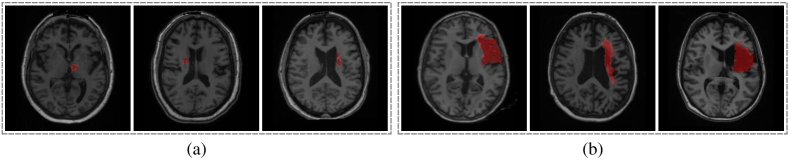

3.6 Visualization Results

Fig. 5 provides qualitative segmentation results for all of the training schemes. Although some of the training schemes, such as Res U-Net, may give false positive results, the overall predictions are accurate for both small and big stroke lesions. Additionally, the outputs of four different schemes (see Section 2.2) are similar with the ground truth, which means all models are able to handle the stroke lesion segmentation task. Besides, boundary areas of ensemble predictions are more smooth compared to four training schemes, indicating some noise false-positive predictions can be suppressed by averaging outputs.

Refer to caption

Figure 5: Segmentation results for different training schemes.